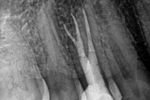

Revisionsbehandlung eines Unterkiefermolaren (37) vor geplanter Überkronung (Dr. Maik Göbbels) Download